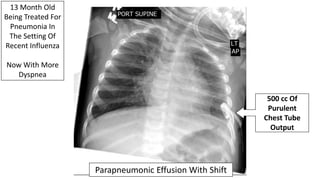

Parapneumonic Effusion With Shift

500 cc Of

Purulent

Chest Tube

Output

13 Month Old

Being Treated For

Pneumonia In

The Setting Of

Recent Influenza

Now With More

Dyspnea